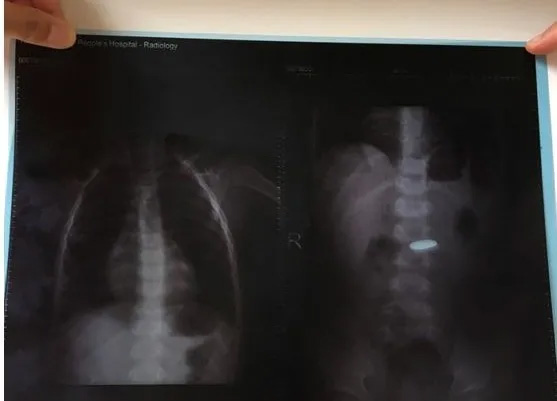

家長擔(dān)心孩子身體情況,帶著患兒來到當(dāng)?shù)乜h醫(yī)院就診,腹部平片提示中腹部異物存留,同時也給患兒多吃易排便的食物及督促患兒多運(yùn)動等方法,觀察10天后仍未發(fā)現(xiàn)硬幣排出。

隨后,家長來到我市兒童醫(yī)院查腹部平片,見異物仍在體內(nèi)??紤]到硬幣已在孩子體內(nèi)存留20余天,家長心急如焚,于是又帶領(lǐng)孩子前往昆明兒童醫(yī)院就診,就診后醫(yī)生考慮異物可能存在胃里,建議患兒家長做胃鏡取異物,患兒家長擔(dān)心孩子太小,做胃鏡時又要行全身麻醉,因此難以決定。